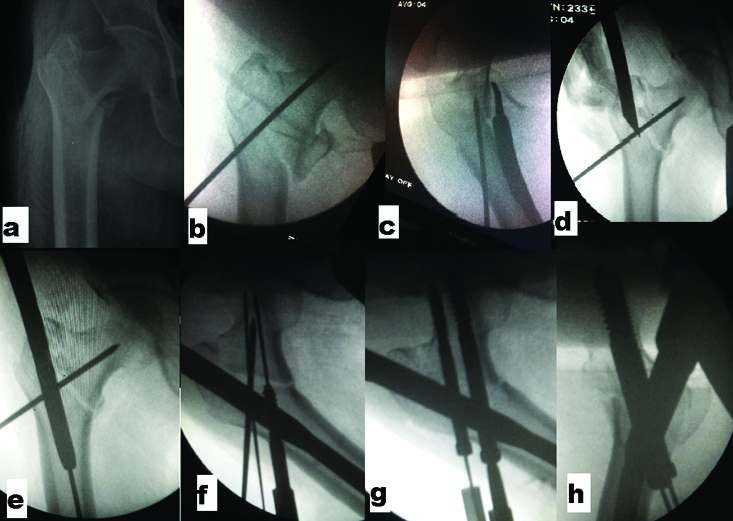

Step by step guide of Steinman pin technique: a) PreoperativeX-Ray; b) Steinman pin fixation in AP view; c) Lateral view; d) Entry by cannulated awl; e) Passage of nail over guide wire behind anteriorly placed pin maintaining reduction; f) Guide pin insertion; g) Lag screw placement after removing Steinman pin; h) Compression by final tightening of screws after releasing traction.

We have learnt over the period that this position of Steinmann-pin avoids collision with reamer or nail by allowing them to pass posteriorly to it due to funnel-shaped geometry of the proximal femoral canal and posterior location of GT in relation to shaft. Steinmann-pin was inserted upto subchondral bone and due care was taken that pin doesn’t pass through fracture or cross anterior or superior neck or subchondral bone. At the site of insertion, anterior placement of Steinmann-pin was ensured clinically by sliding the pin over circumferential surface before deciding final insertion point and radio logically as well. It was withdrawn when inferior lag screw crossed the fracture line [Table/Fig-1,2].

Surgical technique included closed reduction and PFN. Special technique used for all the fractures was provisional fixation by a 3-3.5 mm Steinmann-pin inserted percutaneously after achieving adequate reduction. In all the surgeries; reduction, Steinmann-pin fixation and PFN were done by the same surgical unit. The technique of Steinmann-pin is helpful even in unstable comminuted fractures in achieving equally good results of PFN. It is not useful for Reverse Oblique fractures (AO/OTA 31-A3). Superiority of PFN in those fractures has already been accepted. Therefore, we have excluded such fractures in our study. It can be used in fracture with subtrochanteric extension but it is difficult to use when lateral wall is completely broken. In AP projection, Steinmann-pin passes from lateral cortex to neck and head region being perpendicular to intertrochanteric fracture line. Pin was kept a bit superior in AP projection and in anterior third of trochanteric and neck region in lateral projection.